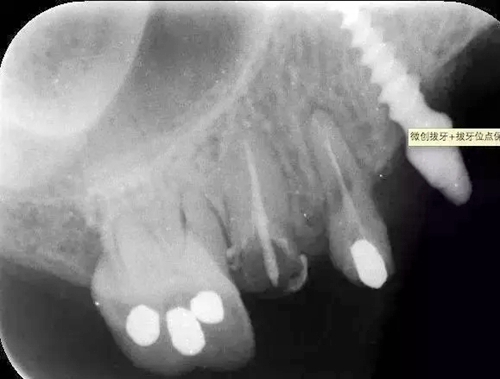

病例:患者,女、44歲,主訴:上頜烤瓷修復(fù)體脫落,要求重新烤瓷修復(fù)。

檢查:14根面旁穿,無法保留,15根長(zhǎng)不足。

處理:14、15微創(chuàng)拔牙+拔牙位點(diǎn)保存術(shù)。

?術(shù)前的x線根尖片